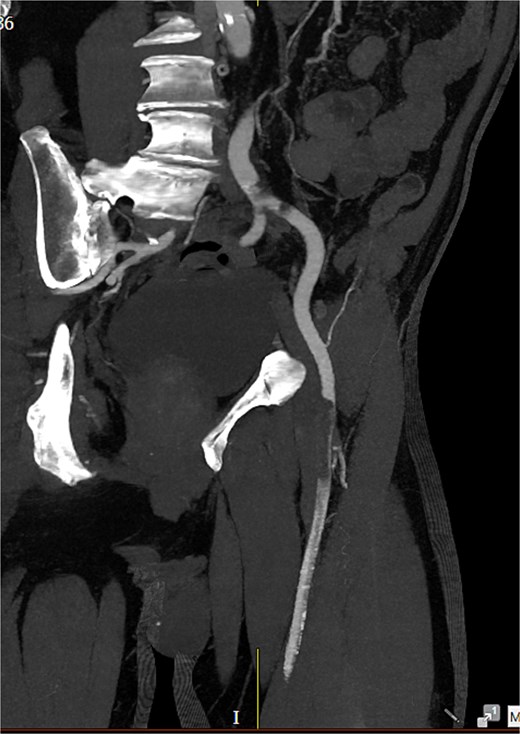

Computed tomography (CT) angiography (Figs 1 and 2) revealed a near-occlusive filling defect at the left common iliac bifurcation. Further embolic material extended into the left common femoral bifurcation, profunda femoris, and superficial femoral artery. An embolic occlusion was also present in the below-knee popliteal artery, extending to the trifurcation, with partial reconstitution of the calf vessels. Emboli were seen in the posterior tibial and peroneal arteries. On the right side, embolic material was noted in the distal profunda and popliteal artery, with further emboli in the tibio-peroneal trunk. The patient underwent bilateral femoral thromboembolectomy.

A near-occlusive filling defect at the left common iliac bifurcation. Further embolic material extended into the left common femoral bifurcation, profunda femoris, and superficial femoral artery.

Embolic occlusion of the below-knee popliteal artery extending to the trifurcation, with partial reconstitution of the calf vessels. Emboli are also present in the posterior tibial and peroneal arteries.